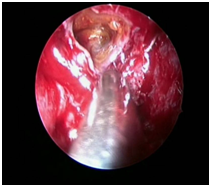

The patient was posted for endoscopic marsupialization of the mucoceles. The mucocele sac from ethmoid sinus was incised and the mucus was drained out (Figure 4 & 5) following which another mucocele sac was identified in the frontal sinus and was drained out (Figure 6 & 7) thus confirming the diagnosis of multiple mucocele introperately.

Figure 6 Intraoperative picture showing right frontal mucocele mucocele

Figure 7 Intraoperative picture showing right  frontal sinus after draining frontal.

Cleared frontal and ethoidal sinuses were examined thoroughly after drainage of the mucoceles (Figure 8). The patient symptoms were relieved postoperatively and the patient was discharged. On follow-up nasal endoscopy showed open sinus cavity, mucosa normal with healthy epithelialization without any sign of recurrence.

Figure 8 Intraoperative picture showing cleared ethoid and frontal sinuses.